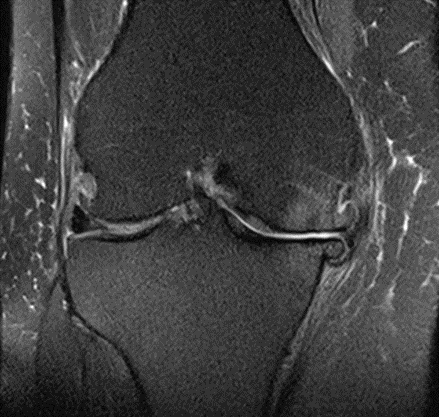

MRI scans illustrating the improvements regarding Group 2 are presented below, showing pre-treatment images with evident cartilage defects, pronounced bone marrow edema, and synovial inflammation, followed by post-treatment scans demonstrating improved joint structure, reduced edema, and decreased inflammation (Figures 12-29).

MRIs of Group 2

Figure 18: Female, 77 years, pre-intervention MRI.

Figure 19: Female of figure 18, two-month follow-up MRI: MSC plus ChondroFiller® liquid.